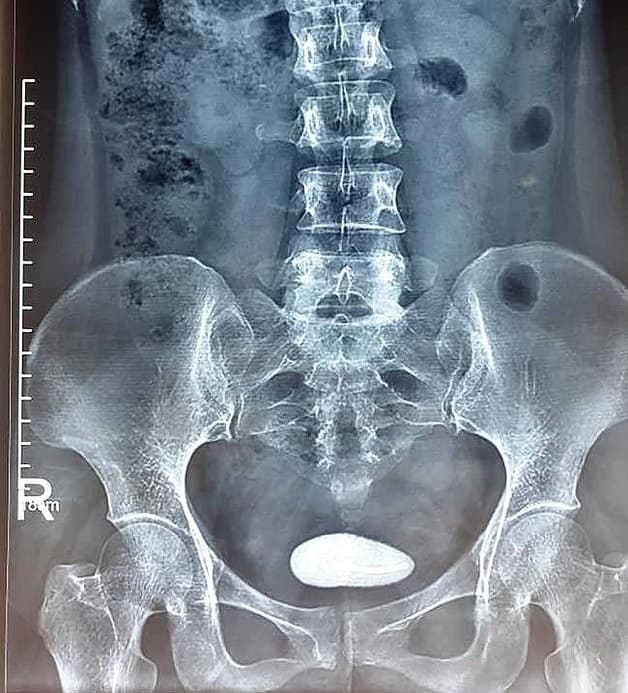

Tán sỏi laser là phương pháp sử dụng tia laser để làm vỡ sỏi thành các viên nhỏ để loại bỏ sỏi ra khỏi cơ thể. Phương pháp này được các chuyên gia đánh giá là kỹ thuật vô cùng tiên tiến đảm bảo an toàn và hạn chế nguy cơ sỏi tái phát. Tán sỏi bằng laser dần dần được lựa chọn thay thế phương pháp mổ mở.

Tán sỏi bằng laser được áp dụng cho sỏi có kích thước và ở vị trí khác nhau. Phương pháp này không để lại sẹo nhờ việc đưa ống soi vào niệu quản.

– Sỏi đài bể thận nhỏ hơn 3cm dạng nhiều viên hoặc đơn thuần

– Sỏi đài bể thận > 3cm

Phương pháp này thường được áp dụng cho trường hợp sỏi nhỏ hơn 3cm